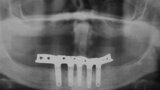

Fig. 12. Prótesis híbrida inmediata con 6 años de evolución y Rx Control a los 6 años.

Fig. 13. Prótesis híbrida inmediata con 6 años de evolución y Rx Control a los 6 años.